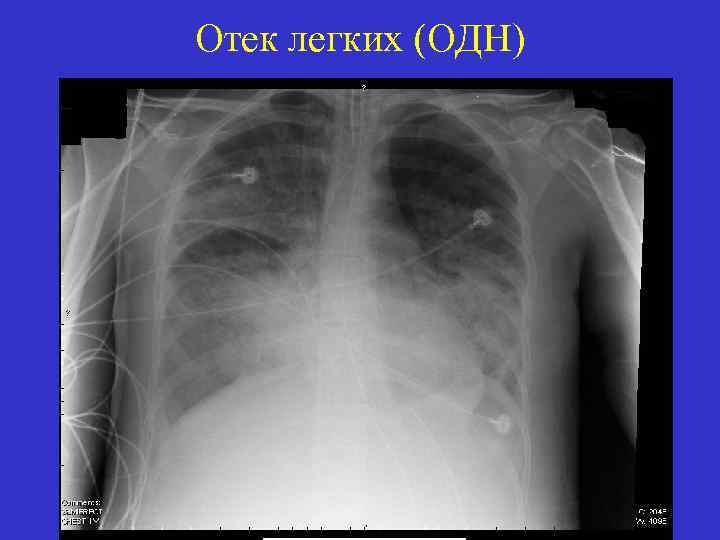

Отек легких (ОДН)